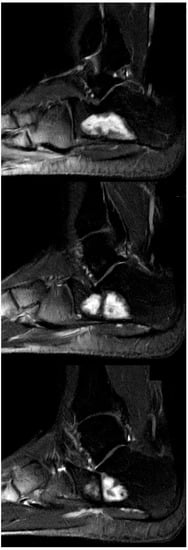

The mean follow-up (f/u) of 24/25 patients was 24.5 months (range 12–91). One patient (case 21) was lost to f/u after the first control six weeks postop. Patients showing complete osseous healing without any defect (Neer type A) in conventional X-rays and no symptoms one year postop were not required to undergo further imaging controls by our clinic, but were contacted by phone and/or mail in January 2021 asking for any additional imaging that was performed in the meantime. A return postage-paid envelope was mailed to the patients requesting the additional imaging. In two cases, the imaging was transmitted digitally. As a result, five more MRI follow-ups of were acquired for the initial Neer type A cases. Only one case (case 6) with MRI performed 91 months after index surgery showed small areas of recurrent SBC (Figure 6a,b), corresponding to a Neer type B healing. In the four remaining cases of initial type A healing, MRI with a mean f/u of 51.2 months (range 36–60) confirmed a complete healing.

Figure 6.

(a) Axial and coronal T2 TSE-weighted MRI showing a large SBC in a 31-year-old professional ballet dancer (case 6). After endoscopic resection, the bone cavity was filled with injectable bone substitute. (b) Sagittal T1-weighted MRI performed 91 months postop, showing two small areas of recurrence of SBC at the medial aspect (bottom image, arrows). The large cyst cavity was filled with QuickSet© injectable bone substitute (marked with a star), showing no signs of osseous remodeling more than 7.5 years after implantation. The patient is currently free of symptoms and still performs at the highest level of professional ballet dancing.